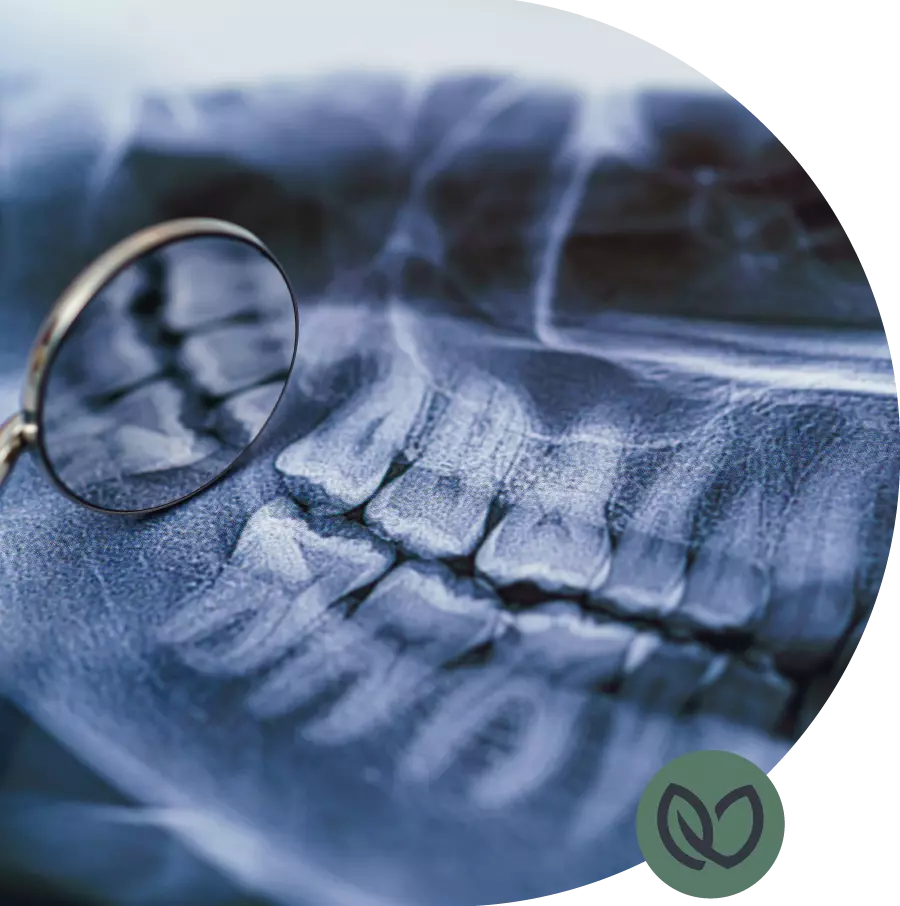

Verstandskiesproblematiek kan worden gediagnosticeerd door een tandarts tijdens een mondonderzoek en het bekijken van röntgenfoto’s. Deze beoordeling kan helpen bij het vaststellen van de positie, groei en eventuele problemen met de verstandskiezen.